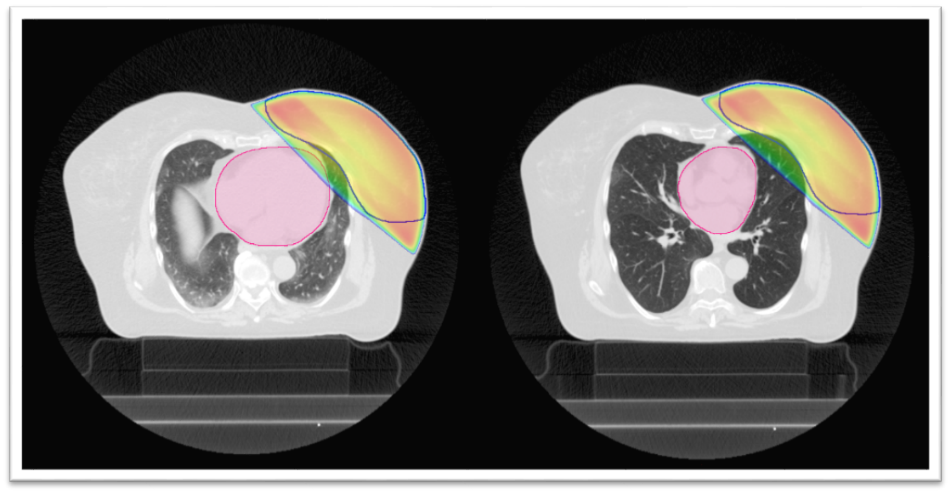

Radioterapie se připravuje pomocí CT vyšetření, na kterém je dobře vidět umístění srdce. Díky němu lze záření zacílit tak, aby procházelo jen prsem a srdce co nejvíce minulo (obr. 1). U většiny žen v případě použití moderních urychlovačů je dávka záření v oblasti srdce tak malá, že nepředstavuje žádné riziko. U menší části je ale srdce blízko u prsu a část záření jím prochází (obr. 2). V takovém případě lze použít ozařování v nádechu (obr. 3), pomocí kterého se srdce opět dostane do bezpečné vzdálenosti. A ozařuje se pouze v nádechu; urychlovač se tedy opakovaně vypíná a spouští. Nádech (polohu hrudníku) kontroluje speciální snímací zařízení položené na hrudníku.

Obr. 1: Srdce je vzdálené od prsu, nehrozí žádné riziko, standardní 3D technika radioterapie fotony lineárního urychlovače. Barevné linie v obrázcích: růžová barva – srdce; modrá linie – objem ozařovaného prsu; barevná plocha – ozářená oblast

Obr. 2 (vlevo): Srdce v blízkosti prsu a část záření skrz něj prochází, proto lékař rozhodne o ozařování v nádechu.

Obr. 3 (vpravo): Ozařování v nádechu („řízené dýchání“) – na ozařovacím plánu je patrné výrazné zlepšení ve smyslu ochrany srdce před zářením.

Barevné linie v obrázcích: růžová barva – srdce; modrá linie – objem ozařovaného prsu; barevná plocha – ozářená oblast